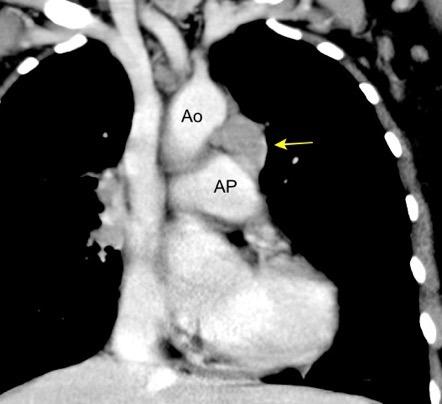

Descrita por Keats representa la interfase de la pleura medial del pulmón izquierdo con el arco aórtico y la arteria pulmonar

Lipomatosis

Keats TE. The aortic-pulmonary mediastinal stripe. AJR. 1972

Keats TE. The aortic-pulmonary mediastinal stripe. AJR.1972 Gibbs JM et al. Lines and Stripes:Where Did They Go?—From ConventionalRadiography to CT. Radiographics 2007

3. Ganglios

4. Desplazamiento de la banda aorto -pulmonar. (Grasa, Adenopatías (Mets, Tb, Ca de pulmón) Hematoma intramural aórtico que sube a los troncos. Drenaje anómalo de VPSI a Vena innominada.